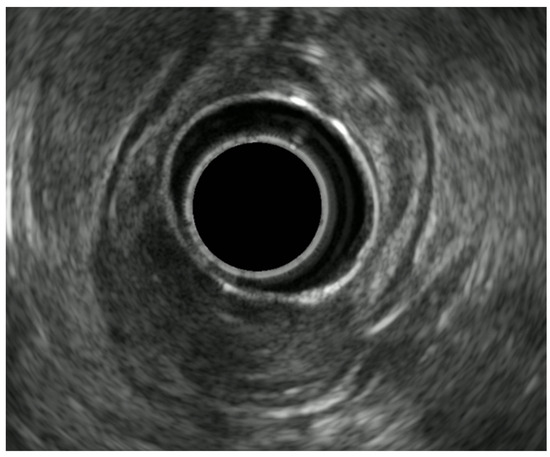

8.3. Rectal Subepithelial Lesions

8.4. Inflammatory Bowel Disease (IBD) and Anal Incontinence